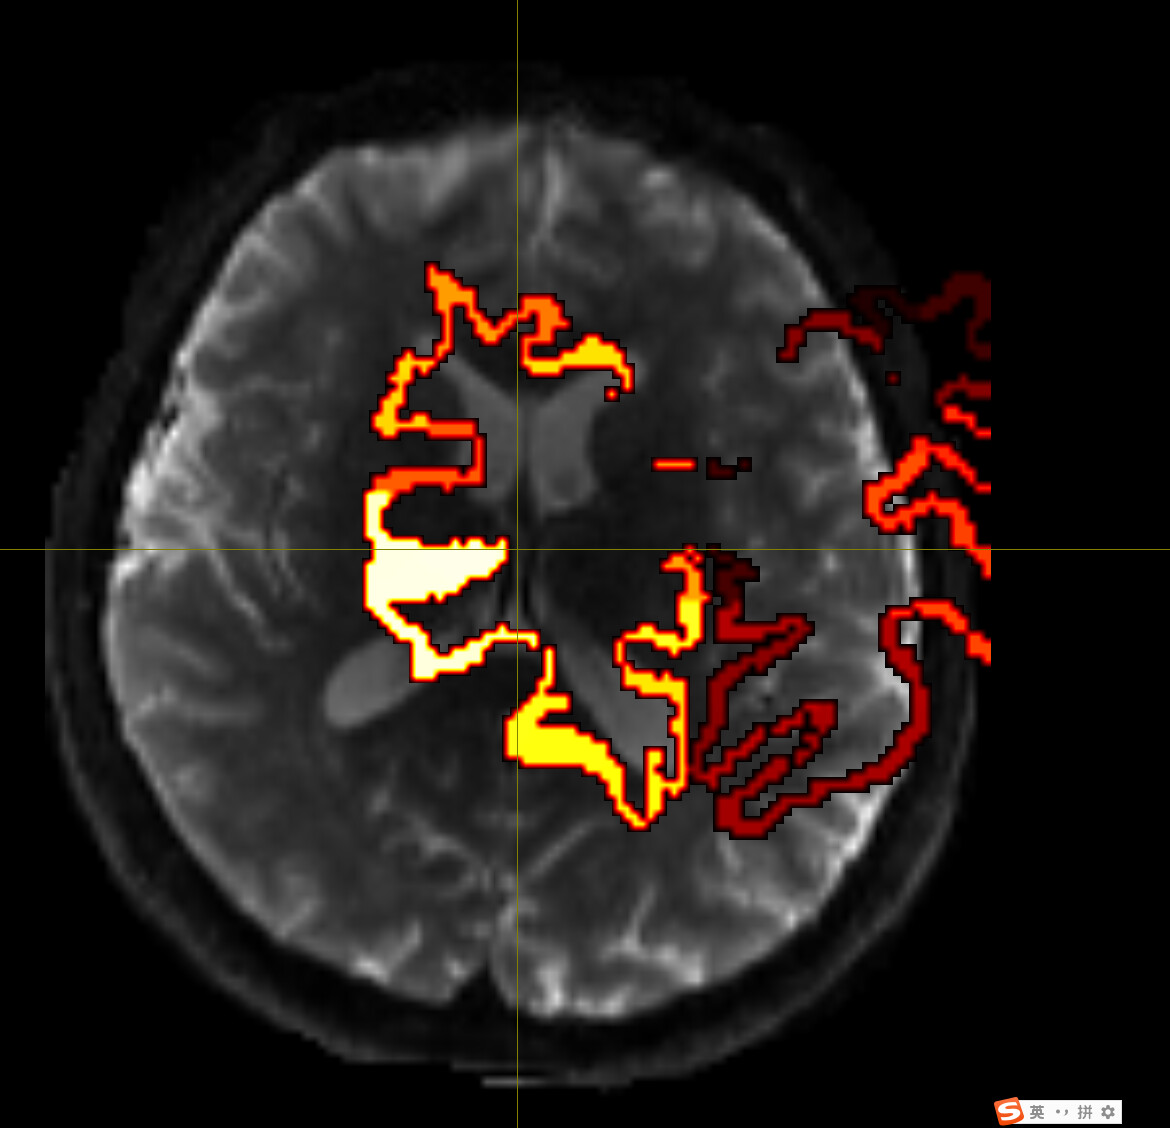

Despite extensive tuning, the final transformed atlas (DKT308_parc.mif) consistently exhibits significant bleeding (invasion) into the white matter (WM) in high-curvature sulcal regions.

I diagnosed this as over-regularization in the FNIRT process (the algorithm prioritizes smoothness over anatomical accuracy).

Visual Evidence

(Please insert the image showing the atlas bleeding into the white matter here)